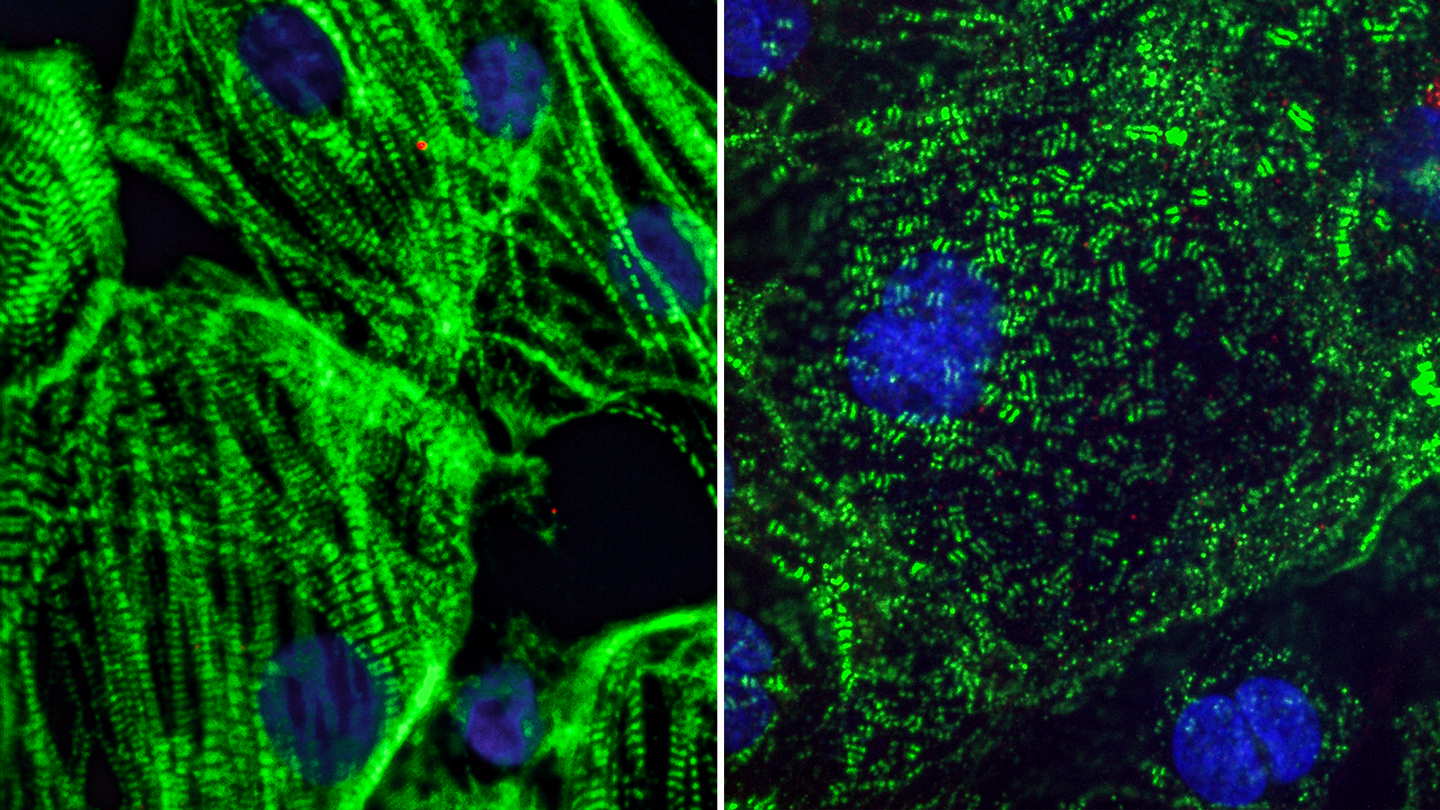

Según las investigaciones del Instituto Gladstone, el coronavirus afecta directamente a los sacrómeros. Los sacrómeros son las fibras responsables de que el corazón lata correctamente. Por ello, cuando estas células resultan dañadas, los latidos del corazón se ven severamente afectados.

Los científicos descubrieron que el virus causante del Covid-19 genera un vacío donde debería estar el ADN de los sacrómeros. Conklin dice que eso “es el equivalente a tener una muerte cerebral” para dichas células, motivo por el cual comienzan a fallar.